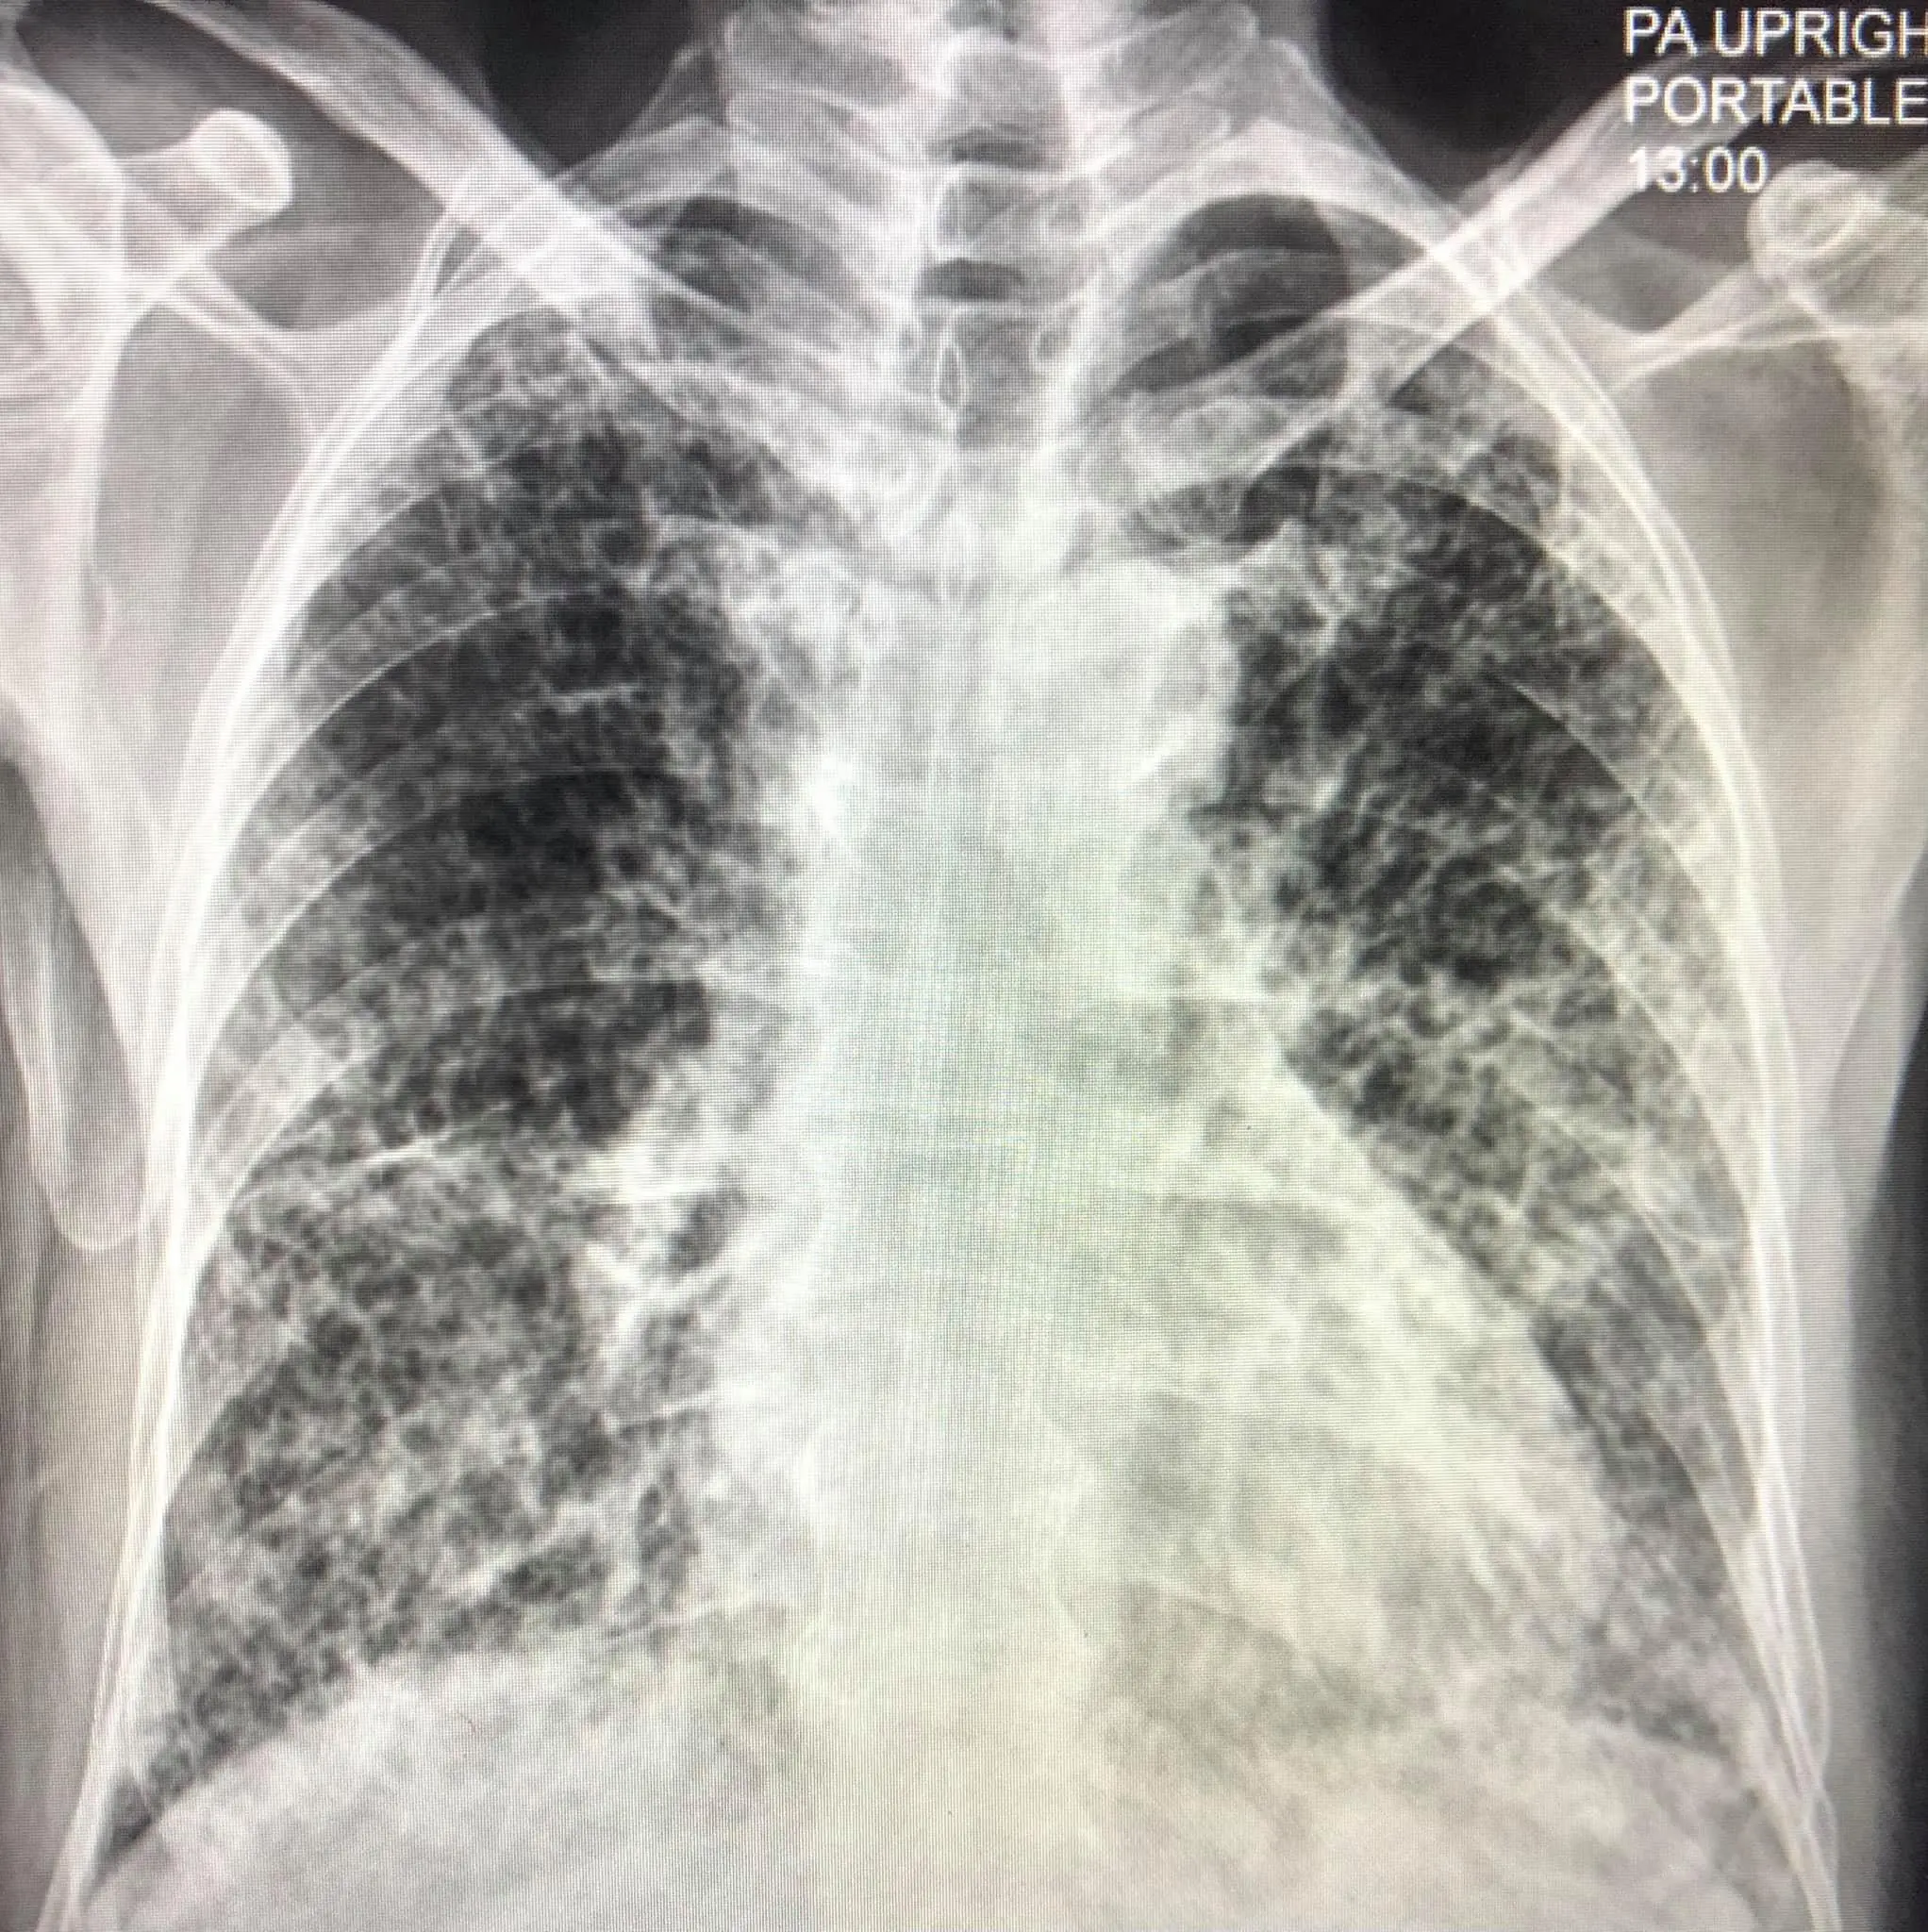

ผู้ป่วยชายไทยอายุ 80 ปี ปกติแข็งแรงดี ไม่มีประวัติป่วยเป็นโรคปอด ไม่สูบบุหรี่ เมื่อวันที่ 16 เมษายน 2564 ป่วยเป็นโรคโควิด-19 โดยลูกเป็นคนนำเชื้อมาให้ผู้ป่วยและคนในครอบครัวรวมทั้งหมด 7 คน เข้านอนรักษาในโรงพยาบาลด้วยปอดอักเสบรุนแรง เอกซเรย์ปอดมีฝ้าขาวทั้ง 2 ข้าง (ดูรูป) ทำคอมพิวเตอร์สแกนปอดพบเนื้อเยื่อปอดอักเสบรุนแรง มีทั้งฝ้าขาว รอยโรคเหมือนร่างแห และลักษณะผิดปกติคล้ายรังผึ้ง กระจายทั่วปอด (ดูรูป) ผู้ป่วยได้รับการรักษาเต็มที่ โชคดีที่ไม่ต้องใส่เครื่องช่วยหายใจ ต้องใช้ออกซิเจนมากถึง 10 ลิตร/นาทีตลอดเวลา นอนในรพ.ถึงวันที่ 22 พฤษภาคม 2564